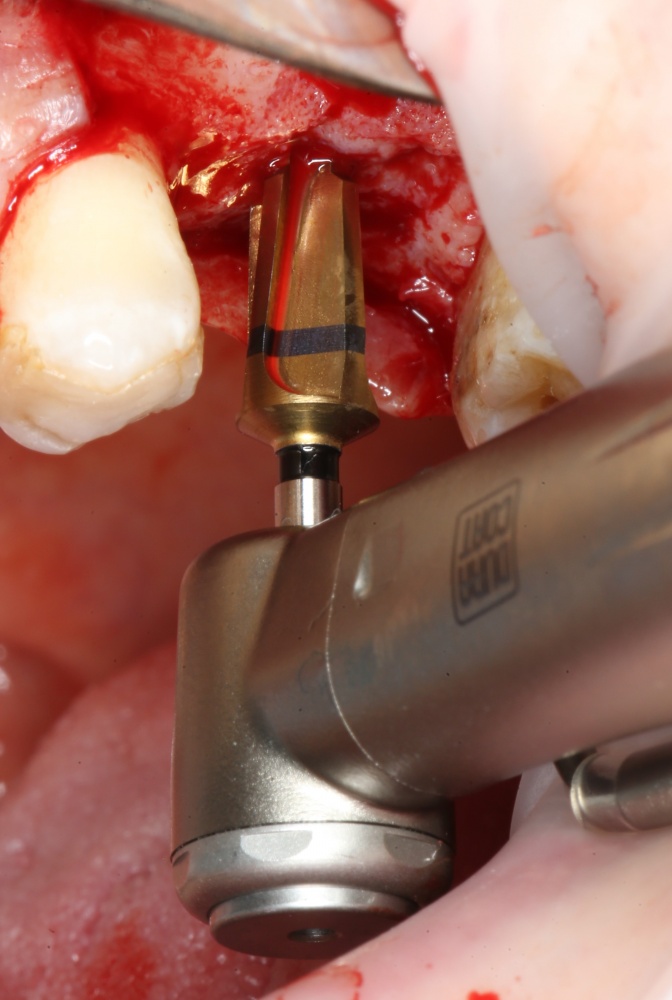

Следующей мы используем фрезу 2.0/3.2:

Такие фрезы — особенность имплантационной системы Astra Tech. Они нужны для того, чтобы не разломать края лунки и сделать переход между фрезами (а мы переходим с 2.0 на 3.2 мм) более точным и плавным, благодаря направляющей 2.0 мм. Однако, пройти лунку такой фрезой на всю глубину удаётся далеко не всегда. В таких случаях используется обычная спиральная фреза диаметром 3.2 мм (с зеленой полоской). Но в нашем случае такой необходимости нет, ибо выше только субантральное пространство, поэтому мы работаем только вот такой двойной фрезой.

Если бы мы хотели поставить имплантат диаметром 4.5 мм, то далее мы перешли бы к кортикальной конической фрезе. Однако ж, я посчитал, имплантат диаметром 5.0 мм в данной клинической ситуации будет более надежным и органичным, поэтому мы продолжаем подготовку лунки. И следующая используемая фреза — 3.2/3.7 — то же самое. что и предыдущая, с направляющей 3.2 мм: